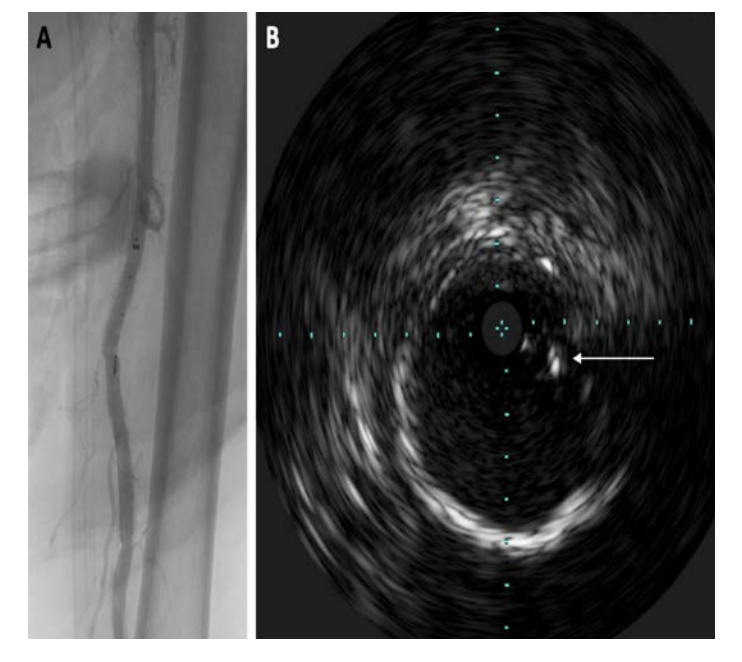

Despite successful embolectomy, attention was now drawn to foreign body retrieval. Initial attempts were performed under the basis of threading a wire though the catheter tip containing the radiopaque marker band and using a small-diameter balloon to fixate the device for retrieval (a “thread the needle” approach). However, the .014-inch wire could not be advanced through the lumen of the radiopaque band, but instead, could only be advanced beside the marker band. A repeat angiogram was performed that revealed the underlying issue: a thin radiolucent defect was noted in the peroneal artery, consistent with a much longer segment than expected for the catheter fragment (Figure 7). Multiple angiograms were performed in a stepwise, cephalad fashion in order to determine the location of the proximal catheter fragment. However, once in the larger diameter popliteal artery, it was difficult to delineate the catheter. Multiple spot views and oblique digital subtraction angiograms still could not delineate the radiolucent catheter.

An astute team member brought up the idea of using ultrasound to identify the fluoroscopically radiolucent catheter. Therefore, intravascular ultrasound (Philips) was performed, and easily and accurately demonstrated the proximal tip to be within the mid superficial femoral artery, a few centimeters distal to the sheath (Figure 8). Using a 15 mm loop snare, the catheter fragment was successfully retrieved, completely intact (Figure 9). The final angiogram demonstrated completely restored flow through the personal artery, with reconstituted pedal arteries (Figure 10). The patient’s foot was warm and her pain had resolved. There were no signs of compartment syndrome after flow was restored.